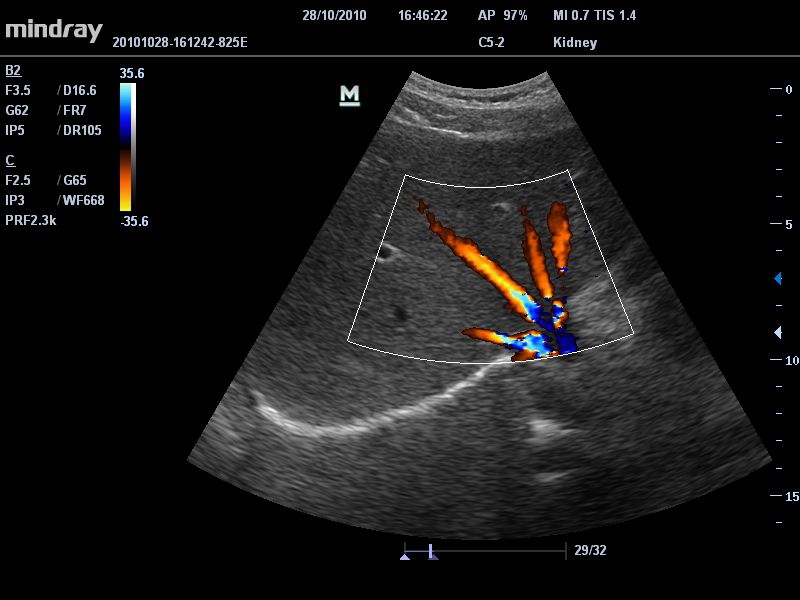

Mindray DC-T6

Ультразвуковая система Mindray DC-T6 – это инновационный аппарат для проведения высокого уровня диагностики с качественной визуализацией и широким спектром применения. Платформа рекомендована для использования в коммерчески многопрофильных медицинских учреждениях и государственных лечебных клиниках.

Цветовой допплер:

Да

• Режимы сканирования: B/M/CFM/PDI/Направленный PDI/PW, HPRF, Тканевая гармоника, М- и цветной М-режим.